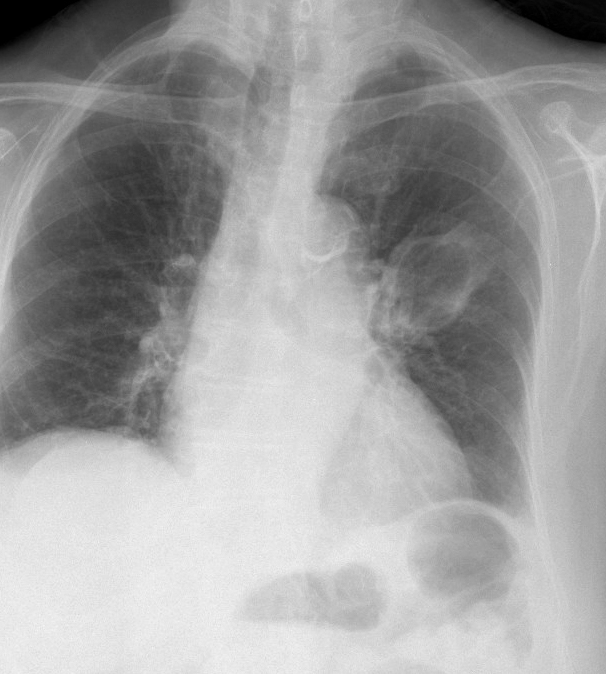

Abscess PA